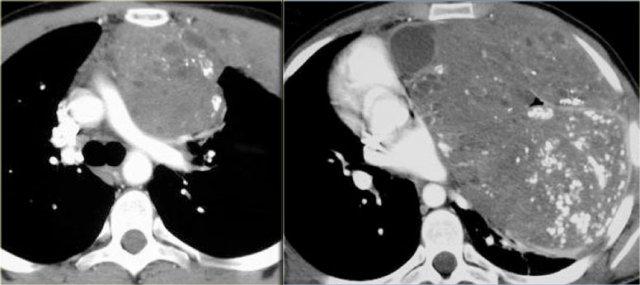

U quái ác tính chiếm 10% tổng số u quái.

Chúng có xu hướng có thành không đều hoặc dạng nốt và thành phần mô mềm chiếm ưu thế.

Chúng cũng có thể cho thấy di căn phổi hoặc gan và xâm lấn thành ngực.